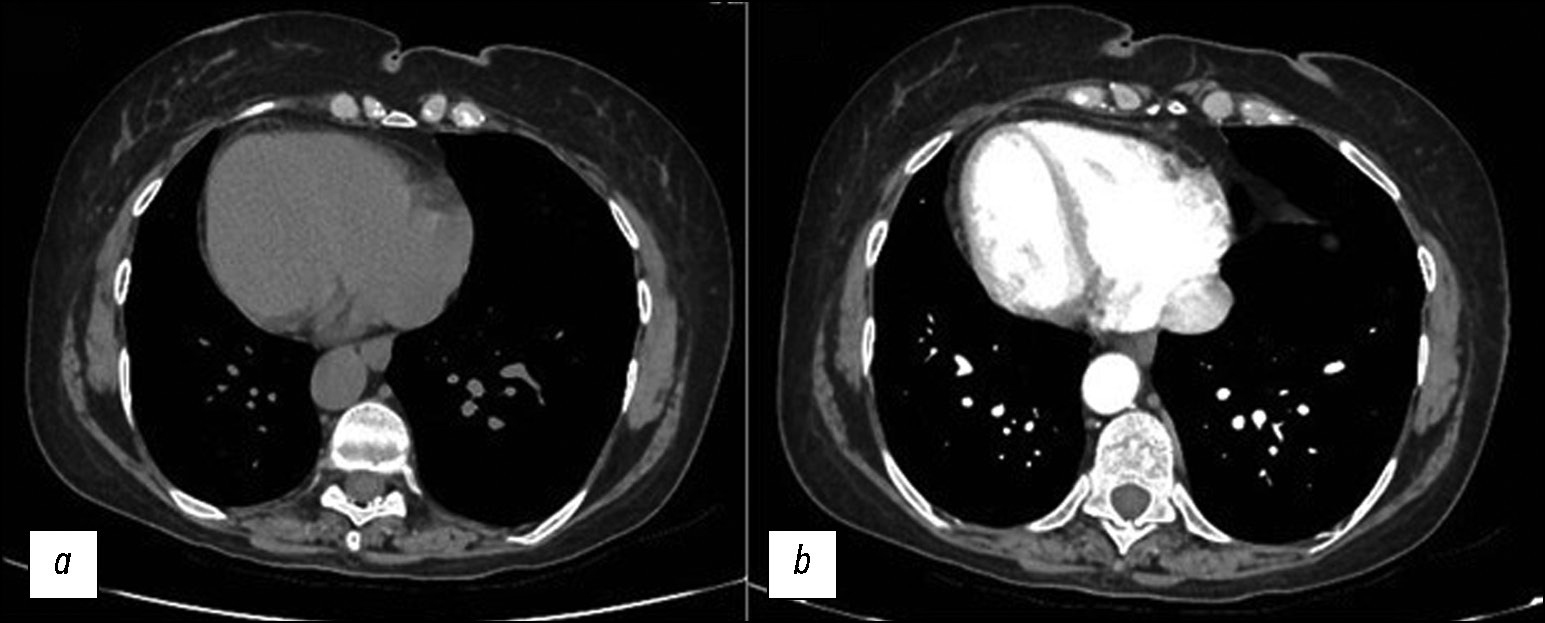

Benign situs inversus totalis of the viscerum is often diagnosed accidentally, rarely in adults, and more frequently in children and neonates, affecting both sexes. In this report, a young female patient accidentally discovered a situs inversus totalis after computed tomography for acute abdominal pain. In this uncommon anatomical abnormality, the major visceral organs are reversed in the opposite direction. This report highlights the importance of being aware of and considering situs inversus in clinical practice, particularly when interpreting imaging findings and planning medical procedures. This is critical for differential diagnosis and comorbidities that may affect those patients.

The cause of situs inversus totalis is still unknown; however, this condition is frequently asymptomatic, particularly in infants, and is sometimes associated with other syndromes. The patient arrived at the emergency department with left flank pain, nausea, and fever. In the first ultrasonography, a strange anatomy was suspected; thus, a contrasted computed tomography was performed. The patient had never had a computed tomography scan before. The identification of situs inversus totalis was unexpected and coincidental; the computed tomography images were carefully examined. In patients with chest or abdominal pain, clinicians may consider situs inversus totalis based on computed tomography, particularly if without clinical and imaging history. This knowledge can help in the differential diagnosis, avoiding unneeded interventions. Moreover, comorbidities that affect several systems, particularly cardiovascular and pulmonary systems, affect quite a few patients with situs inversus totalis, who require careful examination and lifelong monitoring.